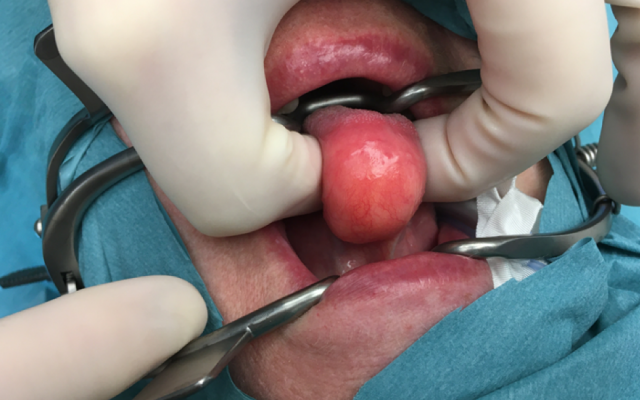

Dit artikel is alleen beschikbaar als PDF.Lees de PDF Artikelinformatie Online verschenen op 23 juni 1956 Citeer dit artikel als Ned Tijdschr Geneeskd. 1956;100:2940-1 Heb je nog vragen na het lezen van dit artikel? Check onze AI-tool en verbaas je over de antwoorden. ASK NTVG Ook interessant Mededelingen Hinderlijke zuinigheid Beeldquiz Hinderlijke zwelling onder de tong Stand van zaken Hinderlijk tranen van de ogen Meer gerelateerd … Reacties Login om een reactie te plaatsen